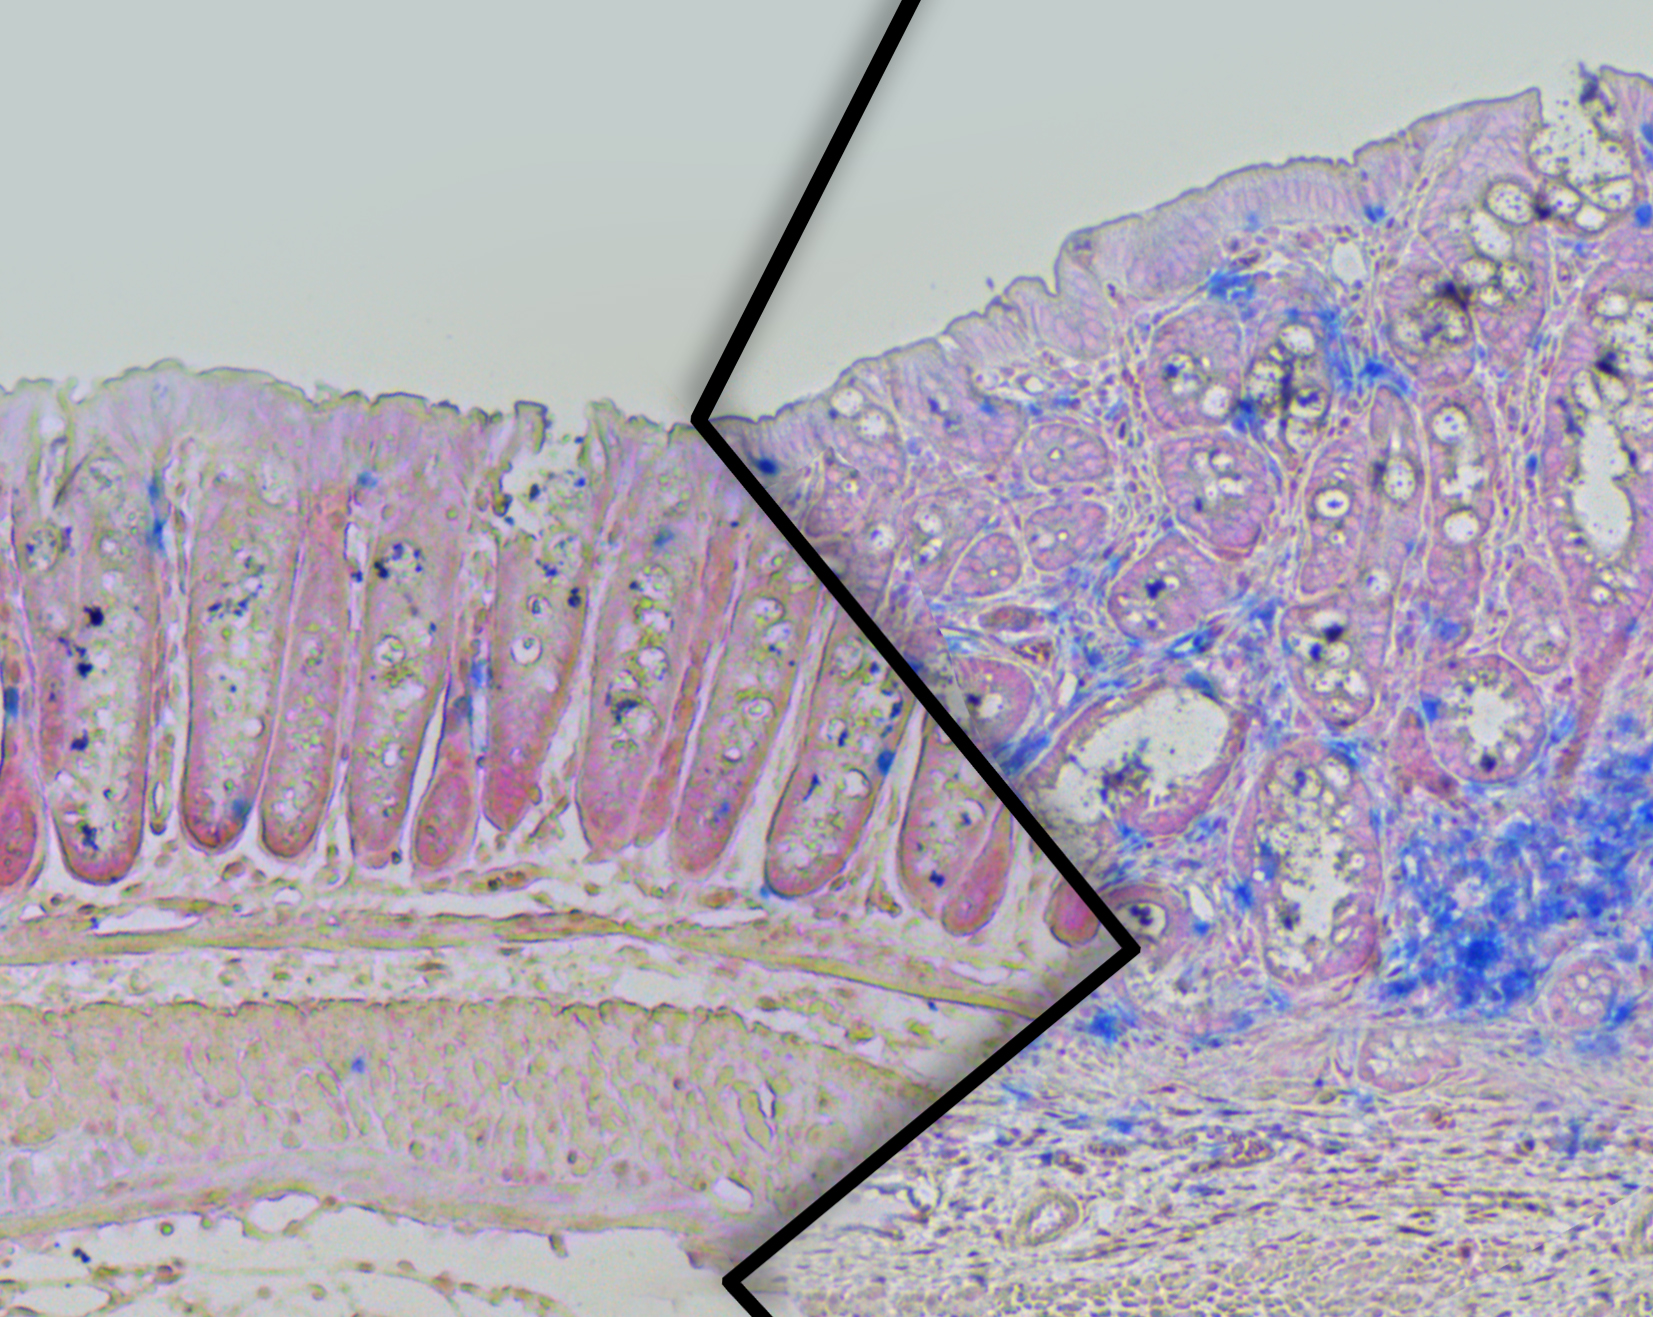

"If the body has to store more and more excess fat, it causes a stress response in the adipose tissue," explains research group leader Dr. Thomas Wunderlich. This stress response alerts the body's immune system, which in turn triggers inflammation in adipose tissue. Chronic obesity puts the body under constant stress and inflammatory signals spread throughout the body. This ultimately leads to a reprogramming of immune cells, changing their function from cancer-fighting to tumor-promoting.

Not only does this study provide evidence on how obesity and colorectal cancer are related, but also additional encouraging findings. "Using mouse models, we were able to identify specific targets for possible therapeutic approaches in humans," explains Claudia Wunderlich. The researchers already have promising results for reducing the risk of disease in obese mice. To do this, they either eliminated specific immune cell populations, or they genetically altered the animals so that certain immune cells could not be reprogrammed in the presence of a high-fat diet. In both cases, the inflammatory response was attenuated, abnormal cells were targeted for removal and the overall development of colon cancer was reduced.